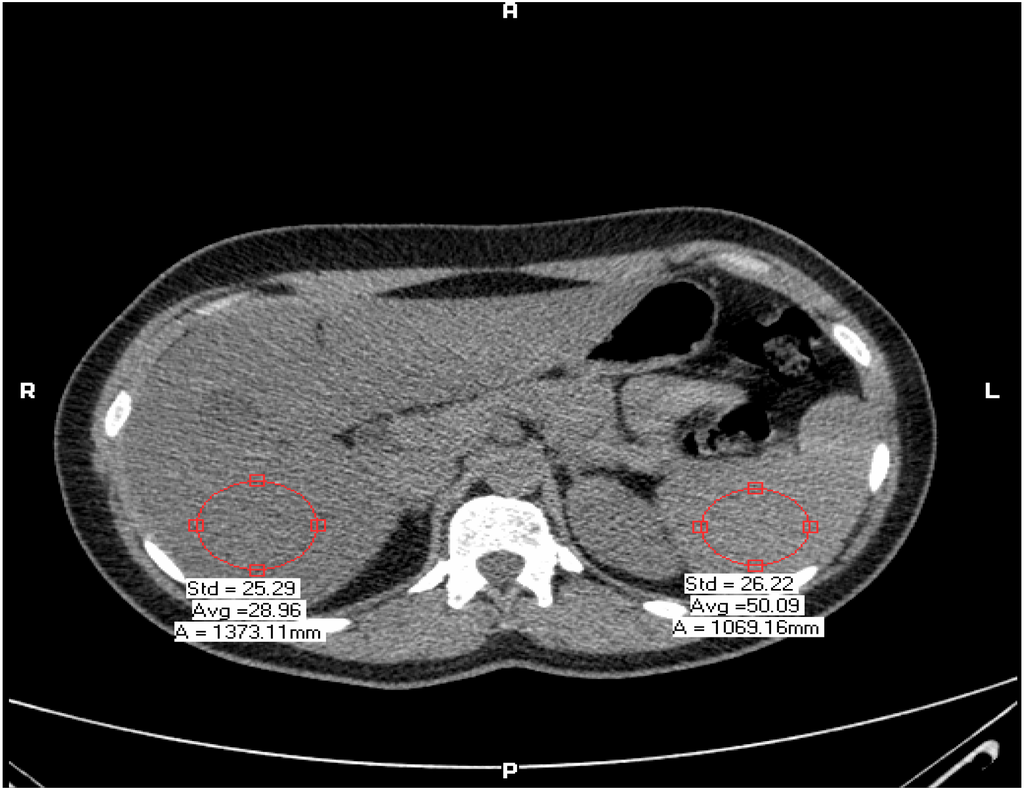

| Liver-Spleen Density (HU) | −15.3 ± 8.9 | +6.8 ± 6.7 | 0.001 |